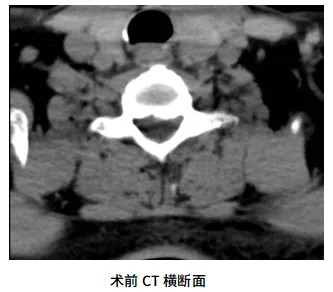

患者為七旬男性,左上肢疼痛麻木難忍3月余,以左前臂、小臂外側為重,經過福州市多家醫(yī)院的口服藥物、針灸、神經阻滯等多種方式的保守治療,患者左上肢的疼痛麻木癥狀始終無法解決。3個月來患者因為疼痛常常入睡困難、夜間頻繁痛醒,極度影響了患者的生活。為了解決病痛,患者慕名找到了修忠標教授,期望修忠標教授團隊能夠為他解決痛苦,讓他恢復正常生活。修教授經過詳細的詢問病史、體格檢查、影像學分析并進行相關的鑒別診斷,確診為:神經根型頸椎病。患者疼痛劇烈,經過3個月的保守治療未取得明顯療效,因此治療方案考慮行手術治療。傳統(tǒng)開放手術創(chuàng)傷大、風險相對較高,且患者高齡,抵觸開放手術?;谝陨系那闆r,修教授團隊與患者及其家屬深入溝通后,決定采用頸椎后路UBE技術實施微創(chuàng)減壓手術。手術由修忠標教授親自主刀,同麻醉科、手術室護理團隊緊密配合完成。麻醉蘇醒后,患者訴左上肢麻痛癥狀有了明顯的改善。

UBE技術(單側雙通道內鏡技術)通過建立兩個微小通道,在清晰的內鏡視野下完成復雜操作,兼具創(chuàng)傷小、出血少、恢復快等優(yōu)勢。頸椎后路UBE手術對操作精度要求極高,需在毫米級空間內完成減壓。此次手術中,團隊將UBE技術應用于頸椎后路,精準摘除脫出的髓核組織,徹底解除脊神經根的壓迫,同時避免對周圍正常結構的損傷。手術切口僅0.8cm左右,術中出血量少,術后患者癥狀明顯緩解,次日即可下床活動 。